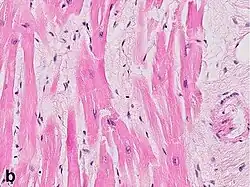

Under the microscope, myocardial infarction presents as a circumscribed area of ischemic, coagulative necrosis (cell death). On gross examination, the infarct is not identifiable within the first 12 hours.[22]

Although earlier changes can be discerned using electron microscopy, one of the earliest changes under a normal microscope are so-called wavy fibers.[23] Subsequently, the myocyte cytoplasm becomes more eosinophilic (pink) and the cells lose their transversal striations, with typical changes and eventually loss of the cell nucleus.[24] The interstitium at the margin of the infarcted area is initially infiltrated with neutrophils, then with lymphocytes and macrophages, who phagocytose ("eat") the myocyte debris. The necrotic area is surrounded and progressively invaded by granulation tissue, which will replace the infarct with a fibrous (collagenous) scar (which are typical steps in wound healing). The interstitial space (the space between cells outside of blood vessels) may be infiltrated with red blood cells.[22]

These features can be recognized in cases where the perfusion was not restored; reperfused infarcts can have other hallmarks, such as contraction band necrosis.[25]

Differential diagnoses for myocardial fibrosis:

- Interstitial fibrosis, which is nonspecific, having been described in congestive heart failure, hypertension, and normal aging.[27]

- Subepicardial fibrosis, which is associated with non-infarction diagnoses such as myocarditis[28] and non-ischemic cardiomyopathy.[29]